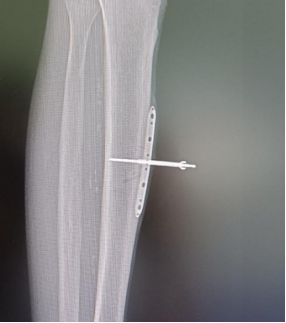

“听到都怕了,大半年住了四次院,年轻人都顶不住,更别说80岁的老人家了。”家属对陈大叔的情况十分担忧。考虑到病人年纪大,病情严重,徐楚江主任果断决定使用最新“骨膜牵张技术配合骨水泥填塞技术(masquelet诱导膜技术)+VSD负压吸引联合技术”进行保肢治疗。

“就像树一样,没有营养供给就会坏死。坏死后如果没有及时的治疗,闭塞就会越来越严重,这名患者足的前后侧血管就出现了严重闭塞,逐渐出现坏死。” 徐楚江解释道,他考虑到患者脚趾部分已经缺血坏死,为了尽最大可能保住患者的脚掌,首先截掉患者已坏死的脚趾部分,填塞骨水泥保住剩余的皮肤,再使用骨膜牵张术逐步植入特殊器械。

骨膜牵张术后,侧肢循环建立

三周后,成功诱导下肢微血管网再生,恢复血运,避免了足部进一步坏死,保肢成功。